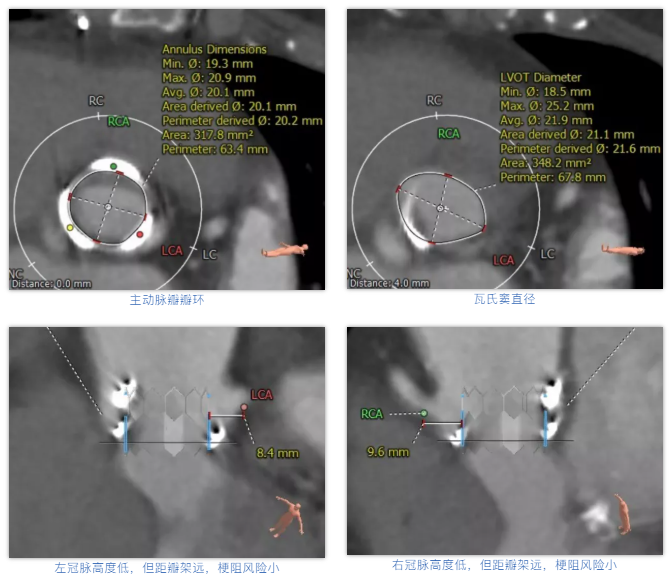

术前经详尽影像学重建和评估,该款人工生物瓣显影不理想,通过CT重建测量瓣环直径,评估冠脉梗阻风险。考虑到患者横位心,主动脉迂曲严重,最终选用经心尖入路,植入21# Renato球扩式瓣中瓣。手术顺利,瓣中瓣植入位置理想,功能表现出色,主动脉瓣峰值流速由术前3.4m/s下降至2.0m/s,平均跨瓣压差由术前32mmHg下降至8mmHg。经食道超声观察无瓣周漏及瓣中反流。